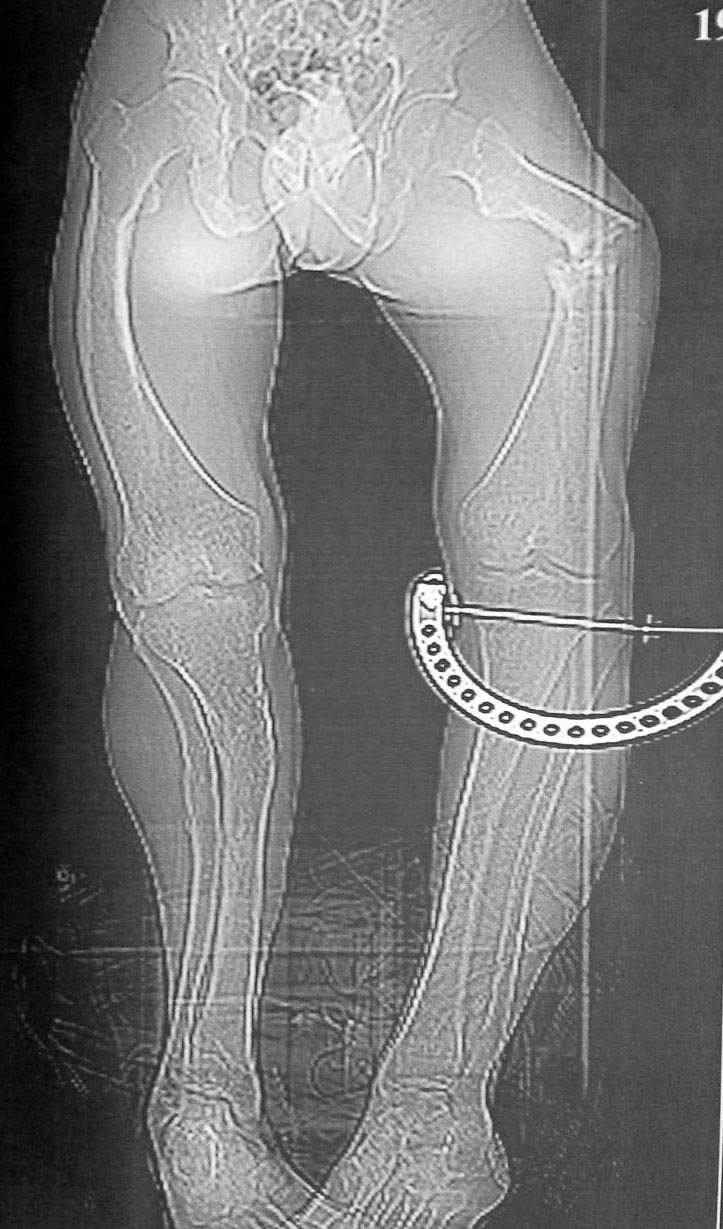

Посмотрите, подойдёт ли туда по размеру гвоздь от большой берцовой кости или от плеча. Они покороче и могут подойти, так как канал у пациента короткий и широкий. Гвоздь будет тонким, по сравнению с его каналом, но этого будет достаточно для стабилизации. Если есть машина Midas Rex с насадками для резки железа, то можно и обычный гвоздьь для бедреной кости подрезать и просверлить в нём дырку дистально.

Рассверливания дла гвоздя будет достаточно, чтобы стимулировать заживление, даже если это сейчас псевдоартроз.

Максим, рассмотрите вариант с TEN максимального диаметра. Наблюдали двоих пациентов, возраст 20 и 18 лет, результат положительный. Штифт будет как "в стакане"